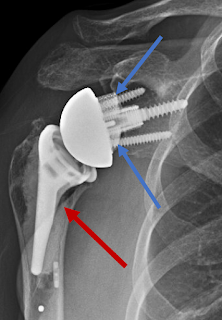

A 75 year old woman had a reverse total shoulder after two failed rotator cuff repair attempts. As we recognize this indicates three risk factors for acromial stress fracture: female sex, advanced age, and rotator cuff disease.

Three months after surgery, she developed pain in her posterior acromion. An acromial stress fracture was diagnosed on subsequent CT scan.

It has been suggested that component selection and position may increase the risk of acromial stress fractures (see for example Lateralized reverse total shoulder: abduction damage to the acromion).

In this case the augmented baseplate lateralized the glenosphere while the varus position of the humeral component lateralized the greater tuberosity.

As a result the tuberosity was at risk for collision with the acromion on abduction.